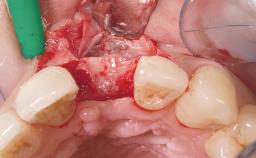

Early Placement of an Implant in a Maxillary Right Central Incisor Site

This 41-year-old female patient was referred to the clinic for the replacement of the right central incisor, since the tooth had developed a root fracture in the long axis that made extraction necessary. The healthy, non-smoking patient was first seen with the tooth still in place. A detailed Esthetic Risk Assessment was performed.The patient was worried about her dental esthetics and had high expectations for a successful treatment outcome from an esthetic point of view. The patient had a medium lip line that displayed parts of the gingiva in the anterior maxilla upon smile.

Soft Tissue Grafting None

Soft Tissue Anatomy Intact Defective

Soft Tissue Contour and Volume Slightly compromised